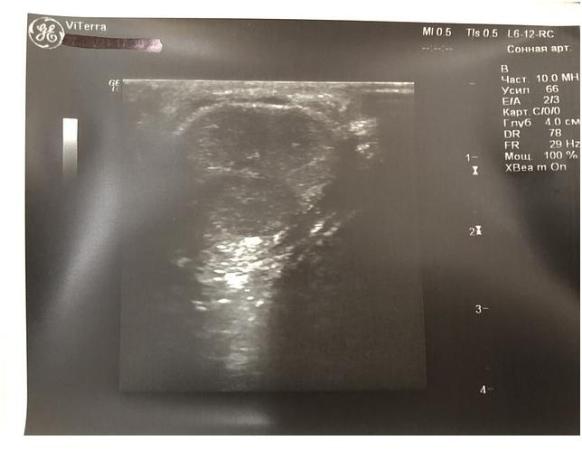

Рядом с ней определяется другая гиперэхогенная тень размерами 0,24х0,04см (фиброзная бляшка), дающая чёткую эхо-тень в виде акустической дорожки.

Рядом с ней определяется третья гиперэхогенная тень размером с просо - 0,08см (фиброзная бляшка), дающая нечёткую эхо-тень в виде акустической дорожки.